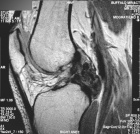

J.G. - 22 year old female with right knee pain

Zoom image: Radiological image Radiological image.